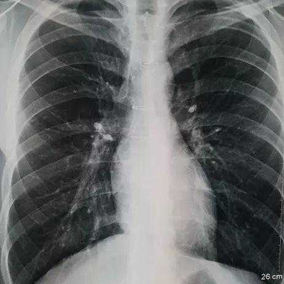

Preoperative Examination

The chest wall exhibits a large area of prominent and bilaterally symmetrical protrusion, predominantly in the upper half. There are also mild depressions on both sides of the lower half of the chest wall.

The patient is a 19-year-old male who underwent surgery for congenital heart disease at the age of 9. During the surgery, the middle part of his sternum was split, compromising the integrity and stability of the chest wall structure. Additionally, inadequate fixation of the chest wall during the closure of the incision led to the development of secondary pectus carinatum, with the chest wall protruding forward within a year after the surgery. Over time, the protrusion became increasingly severe, and by the eighth year after the surgery, the patient began experiencing breathing discomfort.